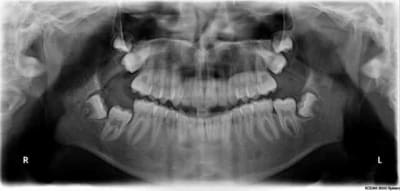

Et la pano qui va avec...

Il semble sur ta pano que ta 16 soit bloquée par la 17, les germes devaient être sacrément à l'étroit sur ce côté droit...

Pour moi, l'idée serait d'extraire la 17, de laisser la 16 prendre la place soit naturellement (ce qui est peu probable) soit par traction ortho, et la 18 pourrait peut-être prendre la place de 17.

La dent lors de son éruption créer le volume de l'os alvéolaire. Il y a une croissance vertical qui continue tout le long de la vie (principalement jusqu’à la fin de l'adolescence, après elle se ralentit mais ne s’arrête pas). Si une dent s'ankylose après son éruption, elle reste figé dans sa position et ne peut pas participer a cette croissance vertical et elle se retrouve infra incluse, c'est pareil avec un implant une fois qu'il est osteointegré il ne bouge plus, c'est la raison pour laquelle on attend la fin de la croissance pour pas qu'il se retrouve en infra clusion (en fait avec le temps il va finir en infra inclusion mais sur une période beaucoup plus longue.) D'après la position de la 16 en rapport avec la 15 on peut déterminer grossièrement a quel période la dent c'est ankylosée.

De manière évidente après son éruption puisqu'elle est sortie de la gencive (sinon elle serait rester incluse), donc après 6 ans.

Ensuite vous voyer que dans le sens antero posterieure la 16 est éloigné de la 15 par un peut plus de 1 mm. La raison est simple, les deux molaires de lait on un diamètre mésiodistale supérieur au deux prémolaire (surtout a la mandibule). Quand elle s’exfolient les 6 se mésialise pour venir en contacte avec les 5. Dans certain cas nous utilisons cette excédent de place en ortho pour résoudre des encombrement incisif (c'est le fameux lee way).

Vue que le 16 est séparé 15 par la distance du lee way on peut en déduire que l'ankylose a eu lieu avant la chute des molaire de lait, donc avant 10 11 ans.

L’ankylose a du se produire à 7,8 ou 9 ans.

Pour la 17, la seconde molaire et soumis au même mouvement dans la direction mésial que la 16 (chez les rats les molaires drifftent en directionn distale). Elle a naturellement continuer a égresser et une fois arriver a une certaine hauteur, la dérive mésiale l'a fait recouvrir en partie la 16. Les 5 ne sont pas soumis au même mouvement, elles se sont incliné la ou il y avait de la place c'est a dire en distale.

Ici ne rien faire est une très mauvaise idée. Ou t'extrait la 17 car tu vas avoir des problème a répétition avec et de toute maniére la mettre sur l'arcade tant que la 16 est en place est impossible, la 16 reste en infraclusion et le patient mâche de l'autre coté.

Envois en consultation ortho, vois avec un stomato si mobiliser la dent est possible sinon extraction.